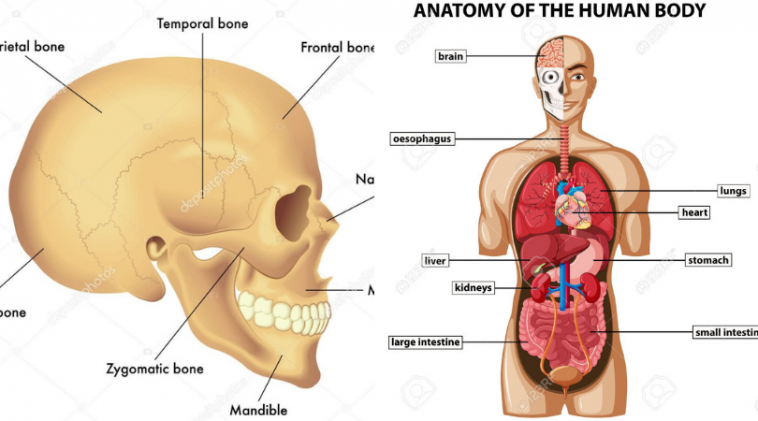

Něco na rozjezd.. O kterou kost se jedná?

kost týlní

kost temenní

kost nosní

kost klínová